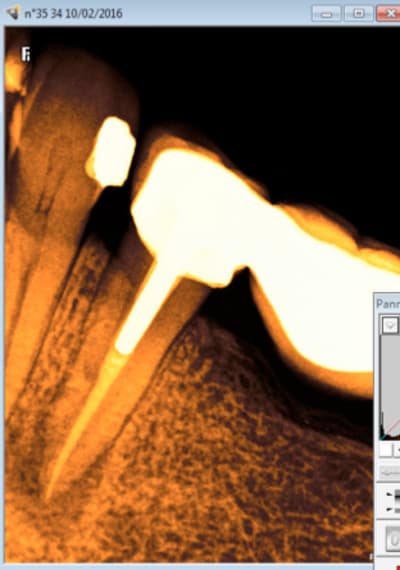

Tu peux me faire un CBCT de 35 ? Il semble y avoir un 4ième bien que le tt endo soit correct.

Je viens de faire une bio sur 45 (pulpite). Et je crois que j'ai ma petite idée sur la cause du 4 ième de 35. -)

Capture d e cran 2016 02 10 10.04 - Eugenol

Capture d e cran 2016 02 10 10.05 - Eugenol